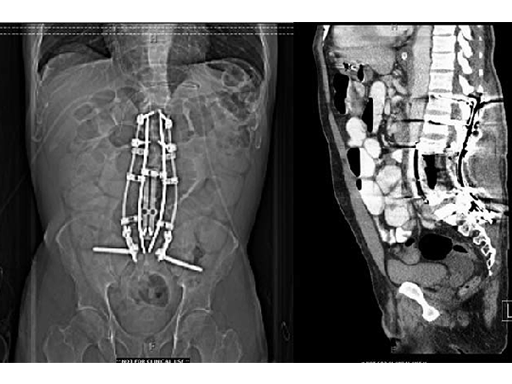

The vertebral body defect was reconstructed with the PEEK distractible cage, anterior plate, screws, and demineralized bone matrix. Final pathology revealed a true en bloc resection with negative margins.

The patient recovered well from surgery, but developed postoperative pneumonia and transient postoperative ileus. But at the time of discharge, the patient was ambulating well and was able to participate in active, inpatient rehabilitation.